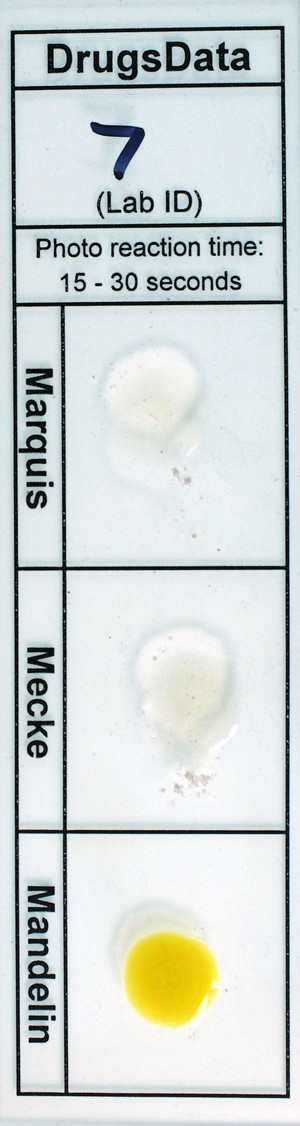

White Powder

Sold as: Diclazepam

Expected to be: Diclazepam

White powder in baggie.